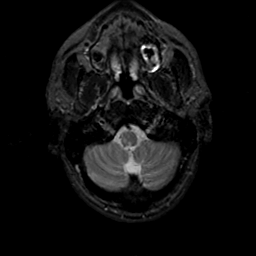

MR Study #19, August 25, 1991 -- Slice #5